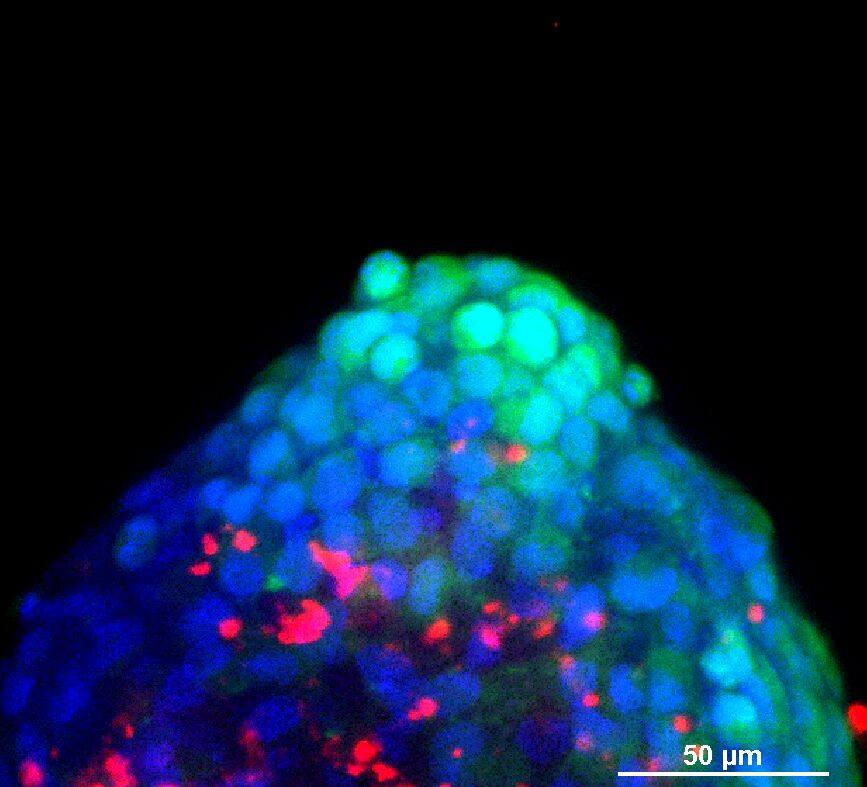

为了生成 3D 球体,将 NCI-H460 细胞(源自非小细胞肺癌)以两种不同的密度接种在超低吸附培养板中:3×103 个细胞/孔或 700 个细胞/孔。在直径分别达到约 400-500 或 150-200 um 后,用细胞毒素剂处理球体 6 天。通过使用钙黄绿素 AM 和碘化丙啶 (PI) 的活/死染色来观察和评估药物的效果。钙黄绿素 AM 是一种细胞渗透性染料,用于测定细胞活性。非荧光钙黄绿素 AM 在活细胞中被细胞内酯酶水解后转化为(绿色)荧光钙黄绿素。PI 是一种红色荧光核染色剂,通常用于检测死亡细胞,因为它不能进入完整的活细胞。最后,使用 Hoechst 染料将细胞核染成蓝色。

我们采用 CrestOptics X-Light V3 转盘共聚焦结合 Prime BSI 相机(Photometrics,像素尺寸 6.5 um)进行采集。我们比较了使用 20 倍空气物镜(CFI Plan Apo Lambda,尼康,0.7 NA 和 1mm WD)和 25 倍硅油物镜(CFI Plan Apo Lambda S,尼康,1.05 NA 和 0.55 mm WD)进行的采集。在图 A 中,我们展示了从总共 150 um 的 Z 堆栈中获得的最大强度投影 (MIP) 图像;特别是,使用 20 倍空气物镜和 25 倍硅油物镜获得了相同的球体。图 B 显示了使用两种物镜获得的 3D 球体同一区域的放大。

使用 20 倍空气物镜和使用 25 倍硅油物镜获得的图像之间的比较(图 A、B 和 C)突出了基于生物应用的透镜选择的重要性。从 20 倍到 25 倍的转换导致分辨率提高(基于 25 倍的 NA 大于 20 倍 NA),这当然会影响图像质量,并且还会导致光折射减少。事实上,浸油通过用更高折射率的介质代替透镜和盖玻片之间的空气间隙,大大提高了显微镜的分辨率,从而减少了光的折射。

在 3D 成像中,样品的折射率与其浸没介质的折射率相匹配对于深层组织观察至关重要。硅酮浸油非常适合透过厚厚的生物样本进行成像;它与细胞和封固剂的折射率非常吻合,与使用普通 20 倍空气物镜获得的图像相比,减少了球面像差,产生了更亮、分辨率更高的图像。

图 B:使用 20 倍空气物镜(左)和 25 倍硅胶物镜(右)获得的 3D 球体同一区域的放大。活细胞用钙黄绿素(绿色)标记,死细胞用 PI(红色)标记。细胞核用 Hoechst(蓝色)染色。这些图像是使用 CrestOptics X-Light V3 转盘获取的。